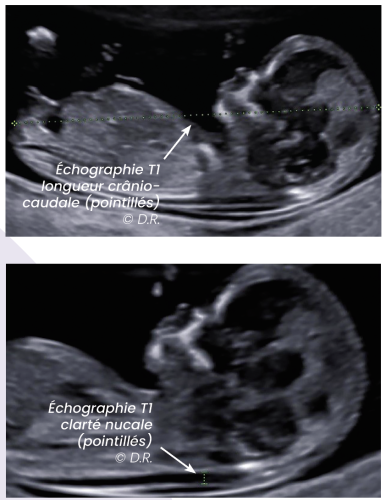

En échographie, la plus fréquente est sans doute la grossesse arrêtée. C’est un moment cruel pour une femme : elle arrive pleine d’espoir et on découvre ensemble que sa grossesse n’évolue pas. Et puis il y a les anomalies fœtales, les trisomies, les malformations cardiaques, les fentes labiales, beaucoup de choses différentes et de gravité très variable. L’échographie dite de datation est la plus précoce, facultative mais fréquente car bien utile pour localiser la grossesse et compter le nombre d’embryons. L’échographie du premier trimestre est essentielle pour dater la grossesse par la mesure de longueur cranio-caudale (LCC), mesurer la clarté nucale (CN) et faire une première analyse morphologique. Le dépistage de la trisomie par marqueurs sériques est proposé mais non imposé.